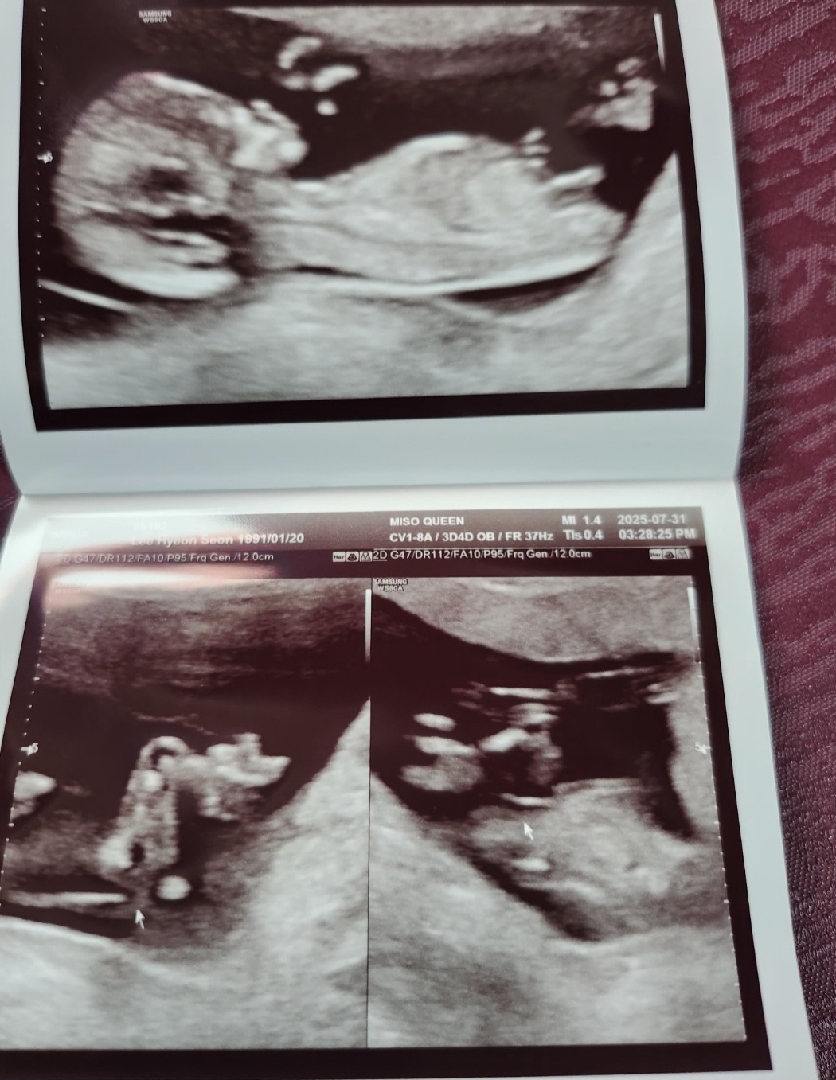

12주에서 13주입니당 초음파인쇄된사진으로 문의드려요 각도법 봐주세욥~!!♡♡